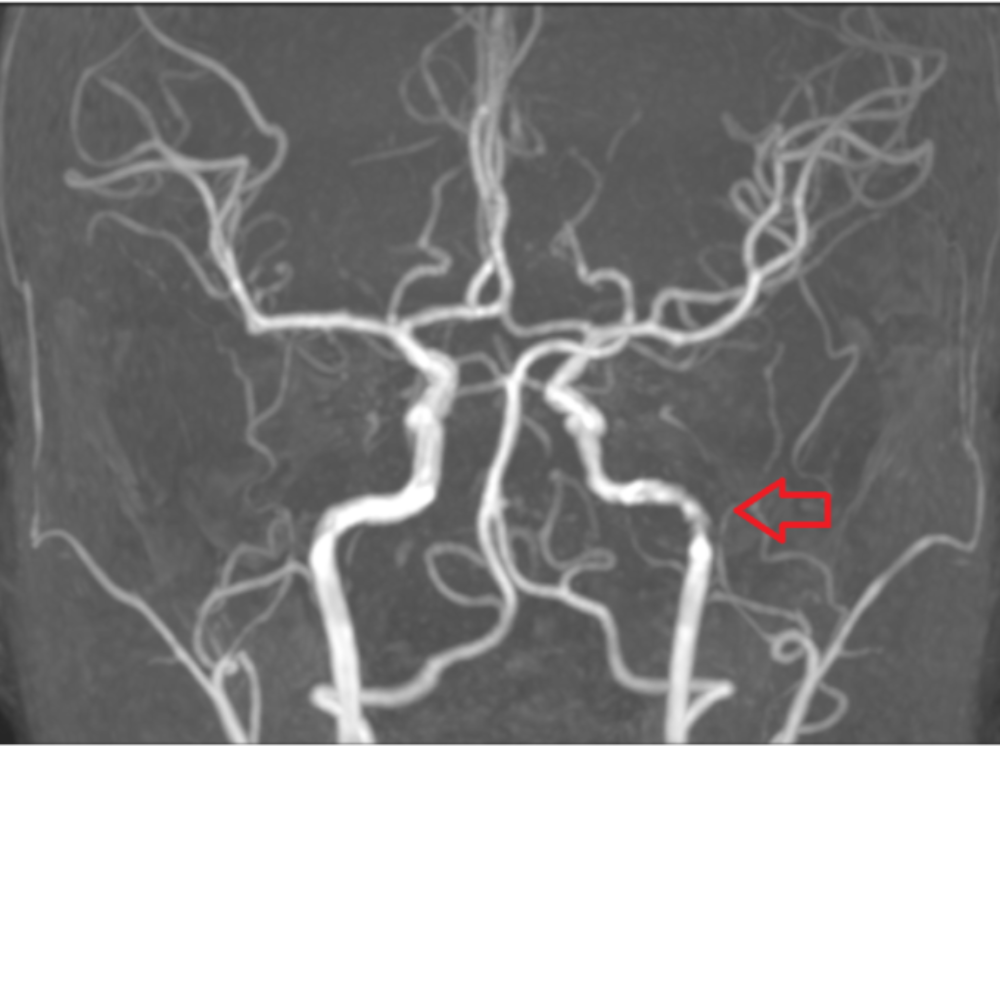

뇌CT 검사에서 발견되지 않는 뇌백질 변성

미세하게 발견된 뇌백질 변성(뇌노화의 척도)

MRI는 뇌종양, 뇌염, 뇌혈관 질환, 미세출혈 등

CT로는 보기 어려운 병변까지 파악할 수 있어,

근본적인 두통의 원인을 찾는 데 매우 중요한 검사입니다.

MRI라고 100% 모든 원인을 찾을 수 없지만,

CT 대비 많은 정보를 주는 것은 확실합니다.

단적으로 뇌노화(치매)의 척도인 뇌백질은 뇌CT에서 확인할 수 없습니다.